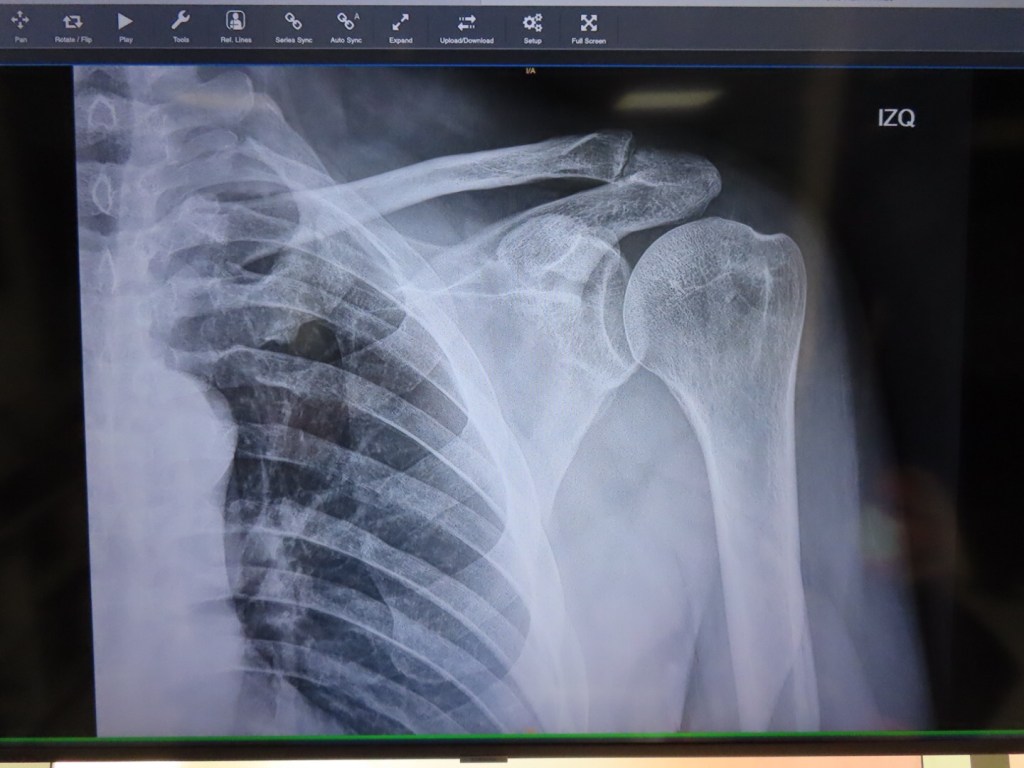

PJ, Alana and another nurse came back. We’ll get you something to ease your anxiety they said. Meanwhile, we crossed the hall for x-rays. This went quickly and easily. You go to another window out front, pay then bring the receipt back and wait. It only took about fifteen minutes. The only catch was that the x-ray tech was the same gal that was doing the MRI. She said not a word to me and gave me a bit of the old stink eye

Dr. Tortosa speaks perfect English and did the most thorough physical exam I’ve had from an orthopedic doctor. We talked for about twenty minutes about patient history then moved to an exam room where he performed a set of tests, range of motion and that kind of stuff. We returned to his office and went over x-rays and MRI images as he explained what we were looking at using models and bones out of a box to make sure we understood. The areas of impingement and inflammation are apparent. We are going to try a shot first and explore surgical intervention later. Will probably do that in the states since I still have good insurance.